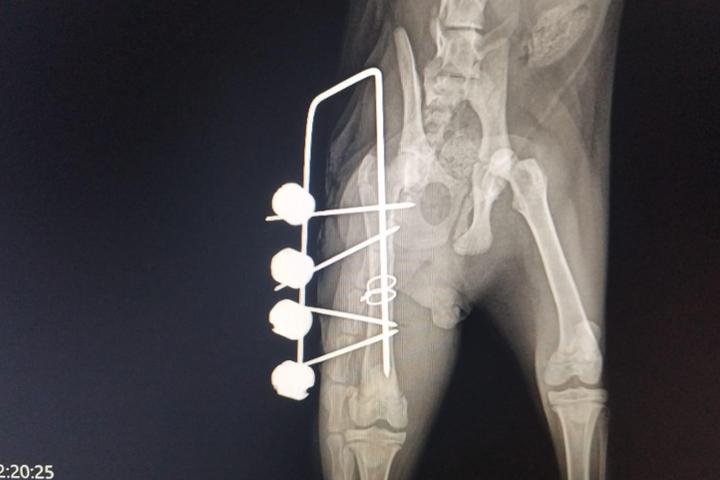

💖 Buenas noticias, pero aún queda camino 💖Nuestro pequeño de 5 meses, gato comunitario de una colonia, fue atropellado y sufrió:🐾 Fractura de fémur y cadera🐾 Luxación cadera👉 Ya ha sido intervenido y ha salido bien de la cirugía, aunque durante la operación entró en hipotermia, por lo que no se pudo realizar la resección de la cabeza del fémur.📌 En un mes y medio se repetirá la radiografía para valorar su evolución.Si todo va bien, en ese momento se retirará el fijador y se intervendrá la cabeza del fémur.Lo importante es que el peque está con nosotros, estable y con fuerzas para seguir adelante 🐾💜.Los gastos veterinarios son muy altos, y necesitamos apoyo para cubrir su tratamiento.

Buenas noticias, pero aún queda camino Nuestro pequeño de 5 meses, gato comunitario de una colonia, fue atropellado y sufrió: Fractura de fémur y cadera Luxación cadera Ya ha sido intervenido y ha salido bien de la cirugía, aunque durante la operación entró en hipotermia, por lo que no se pudo realizar la resección de la cabeza del fémur. En un mes y medio se repetirá la radiografía para valorar su evolución.Si todo va bien, en ese momento se retirará el fijador y se intervendrá la cabeza del fémur.Lo importante es que el peque está con nosotros, estable y con fuerzas para seguir adelante .Los gastos veterinarios son muy altos, y necesitamos apoyo para cubrir su tratamiento.